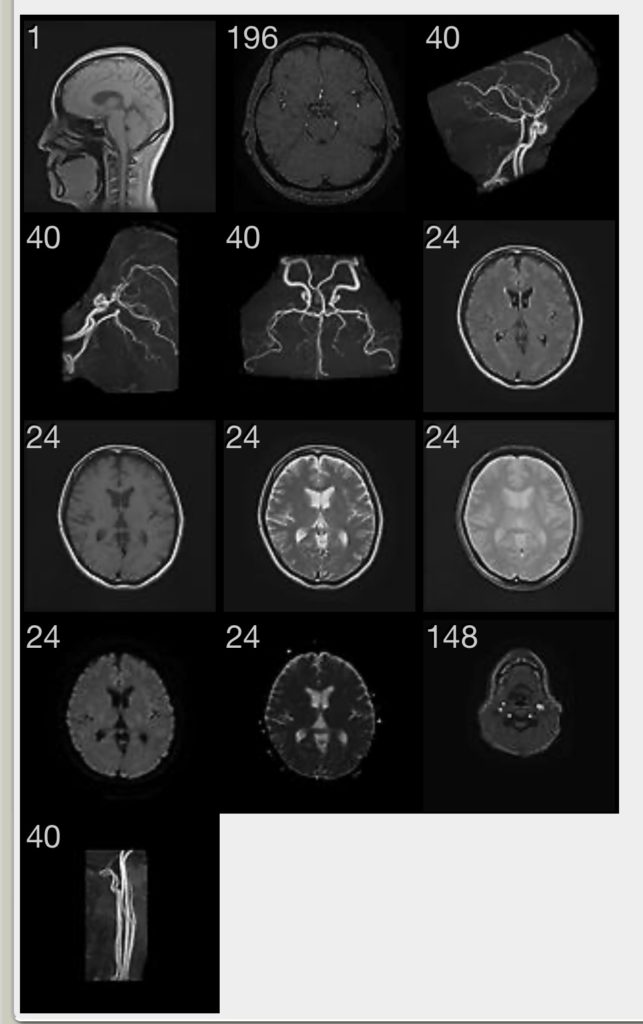

で、これが送ってくださった画像。よくわからないけど、「正常ですよ~~」と先生が教えて下さってなんだかほめられた気分。

アプリでスマホに画像を送ってくださるなんて便利ですね。すごい。